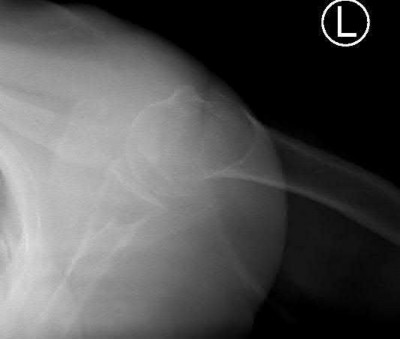

A 55-year-old patient presents with a slowly enlarging, painful mass in the proximal humerus.

Biopsy reveals a hyaline cartilage matrix with cellular atypia, confirming a diagnosis of central conventional chondrosarcoma. Which of the following genetic mutations is most frequently identified in this specific tumor?

Explanation

Mutations in the isocitrate dehydrogenase genes, IDH1 and IDH2, are found in up to 50-60% of central conventional chondrosarcomas and enchondromas. EXT1 and EXT2 mutations are characteristic of multiple hereditary exostoses (osteochondromas). GNAS mutations are seen in fibrous dysplasia. TP53 and RB1 mutations are hallmark aberrations in osteosarcoma.